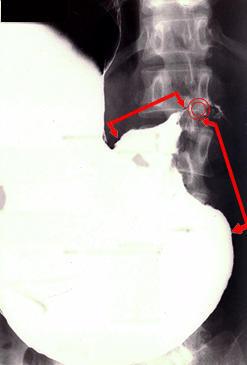

疾患(病理主体)の分類悪性上皮性腫瘍/腺癌

部位(臓器別)胃(部位)/前庭

検査方法X-P

腫瘍の肉眼分類3型(潰瘍浸潤型)/

病変の最大径(ミリ)40以上

腫瘍の深達度s(a)